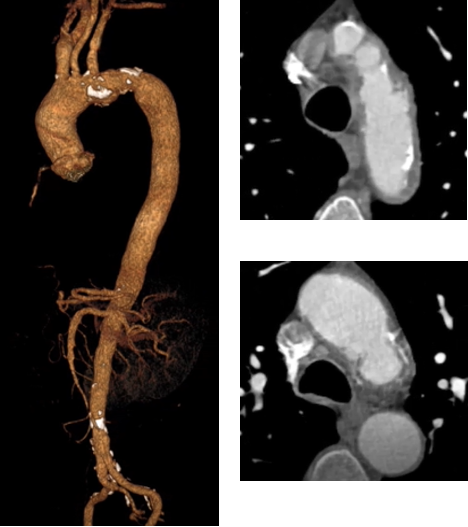

★ 病例3

顾某,男,50岁,“胸背部疼痛3天”入院,主动脉CTA提示:主动脉夹层(多发性主动脉弓部溃疡);2.降主动脉假性动脉瘤;3.主动脉壁内血肿(B型)。

术前CTA